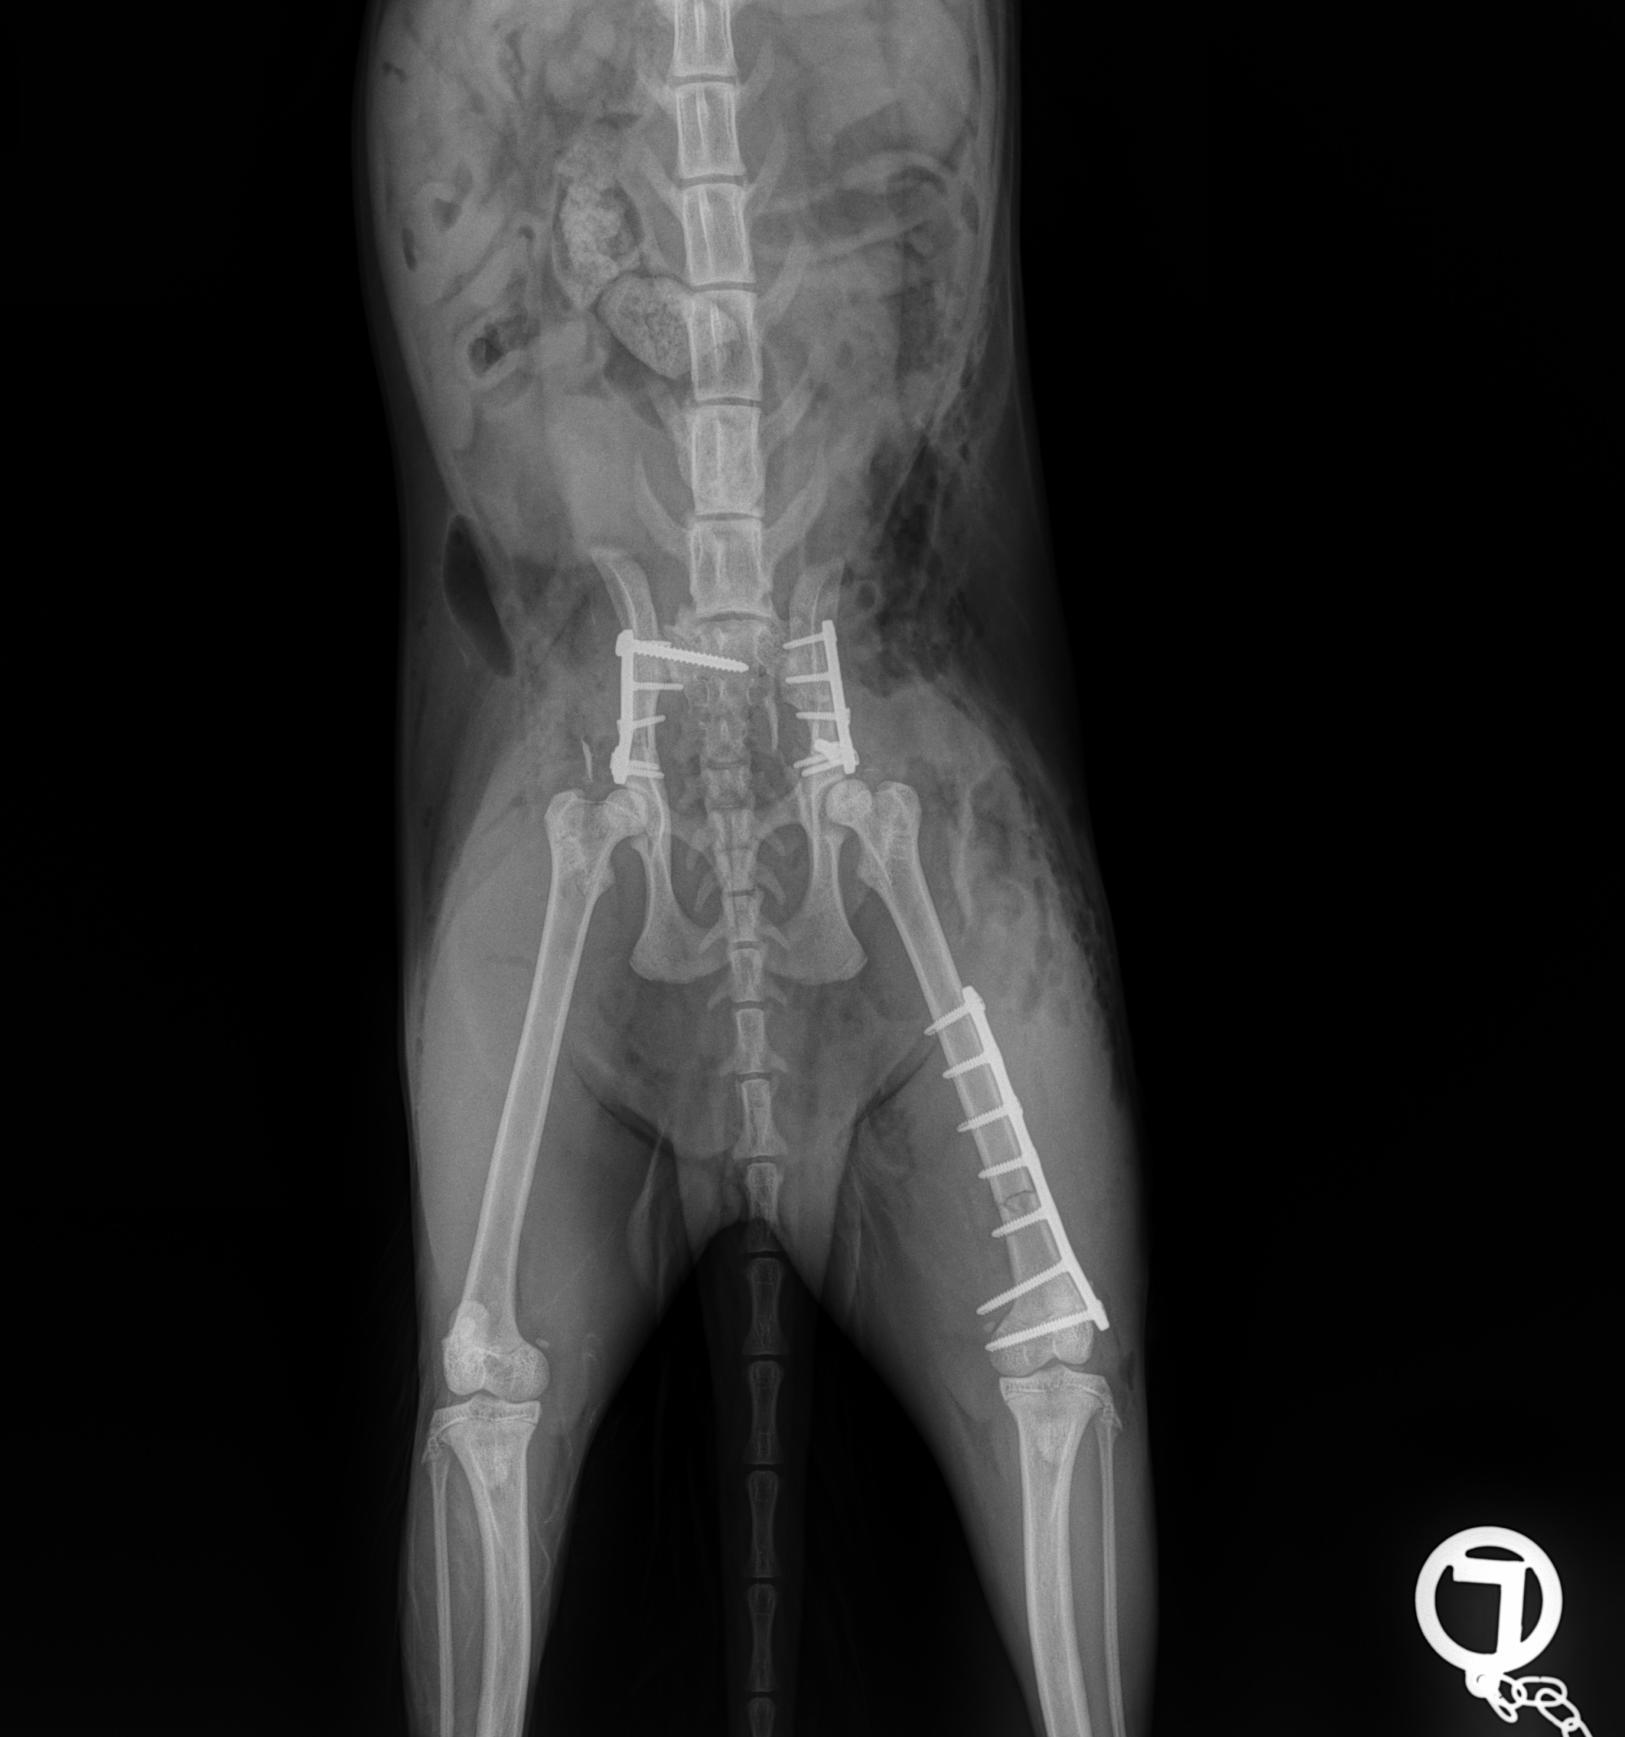

Day 1: He had to fix a humerus spiral fracture (left) with a LeiLOX bridge plate. Furthermore, he diagnosed a femur transverse fracture. Dr. Sonntag then used a 7-hole LeiLOX plate to repair this fracture, and do several emergency soft tissue surgeries.

Day 2: Repair of two iliac bone traverse fractures (left and right) with LeiLOX L-plates. Finally, several soft tissue surgeries were performed.

(Surgery time: 1:50 hours)